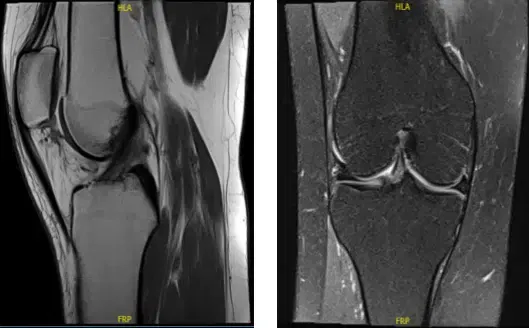

The MRI was reviewed and discussed; for her right knee pain it has no fracture, dislocation, marrow replacement process, or osteochondral lesion is identified.

The distal quadriceps tendon, patella, and patellar ligament appear within normal limits. 0.6 x 0.9 x 1.7 cm lobular oval lesion that is low signal on TI and heterogeneous signal on T2 is identified between the lateral patellar facet and anterior femur in the patellofemoral joint region and may represent fibrotic changes.

The anterior cruciate ligament, posterior cruciate ligament, medial collateral ligament, and lateral collateral ligament are intact. No soft tissue mass or abnormal signal in the musculature is identified. An oblique tear in the posterior horn of the medial meniscus is identified. The lateral meniscus is intact with no tear identified.

With impression of Oblique tear in the posterior horn of the medial meniscus. 0.6 x 0.9 x 1.7 cm lobular oval lesion that is low signal on TI and heterogeneous signal on T2 is identified between the lateral patellar facet and anterior femur in the patellofemoral joint region and may represent fibrotic changes.

MRI Right knee non-contrast